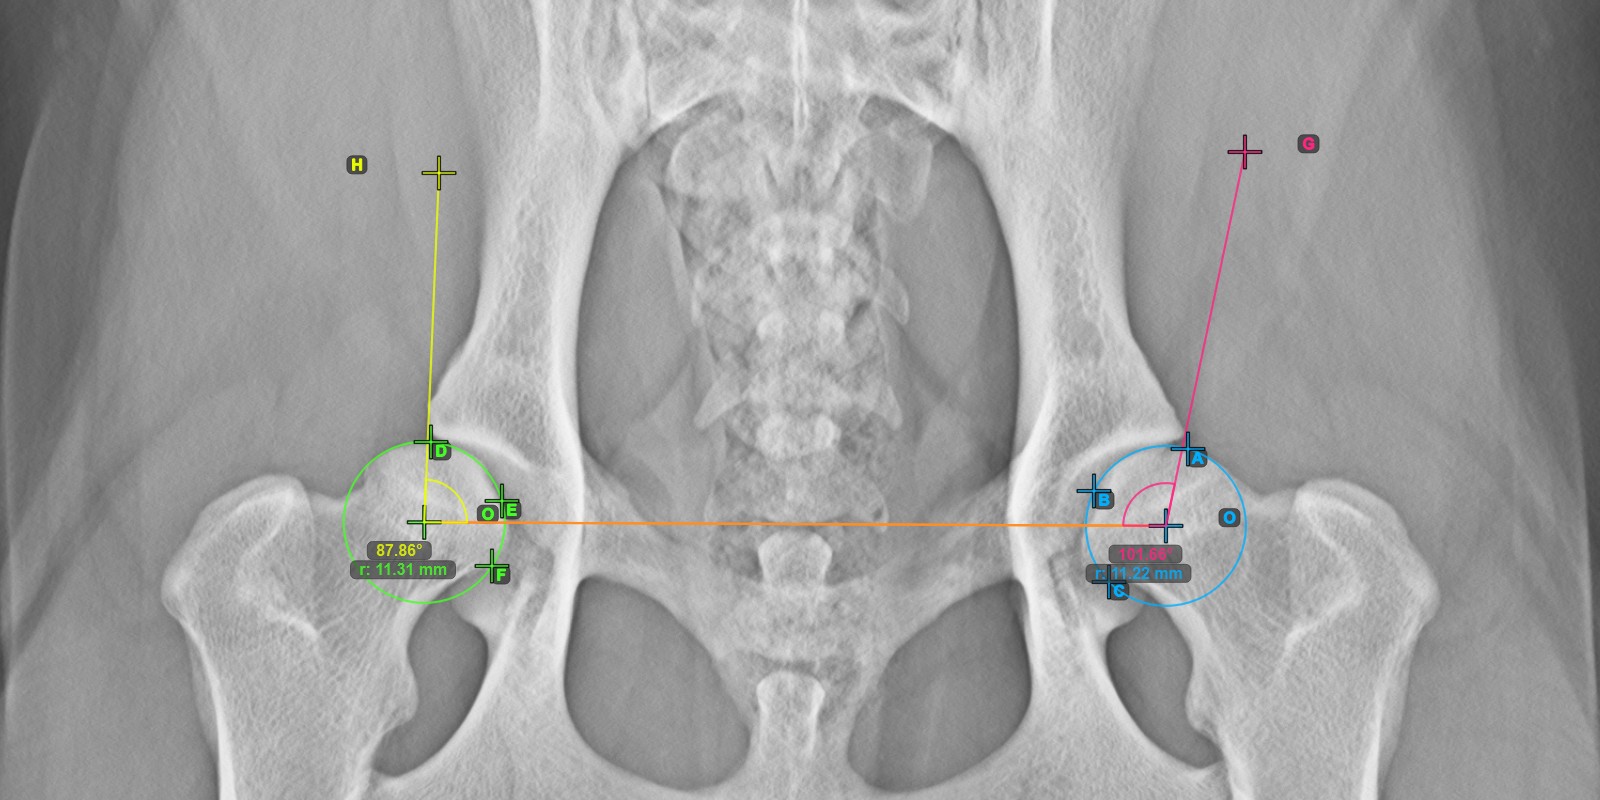

Mark the three points on the articular surface of the right Caput Femoris (outside of the Fovea Capitilis). Regardless of the order, make sure to mark the most cranial point, the most caudal point and the midpoint of the femoral head. A circle will be automatically constructed based on the three placed points.

The origos of the two circles will also automatically be connected by a line, specifying the initial side of the angles yet to be constructed.

The image below depicts the typical placement of the three points on the articular surface of the right Caput Femoris.